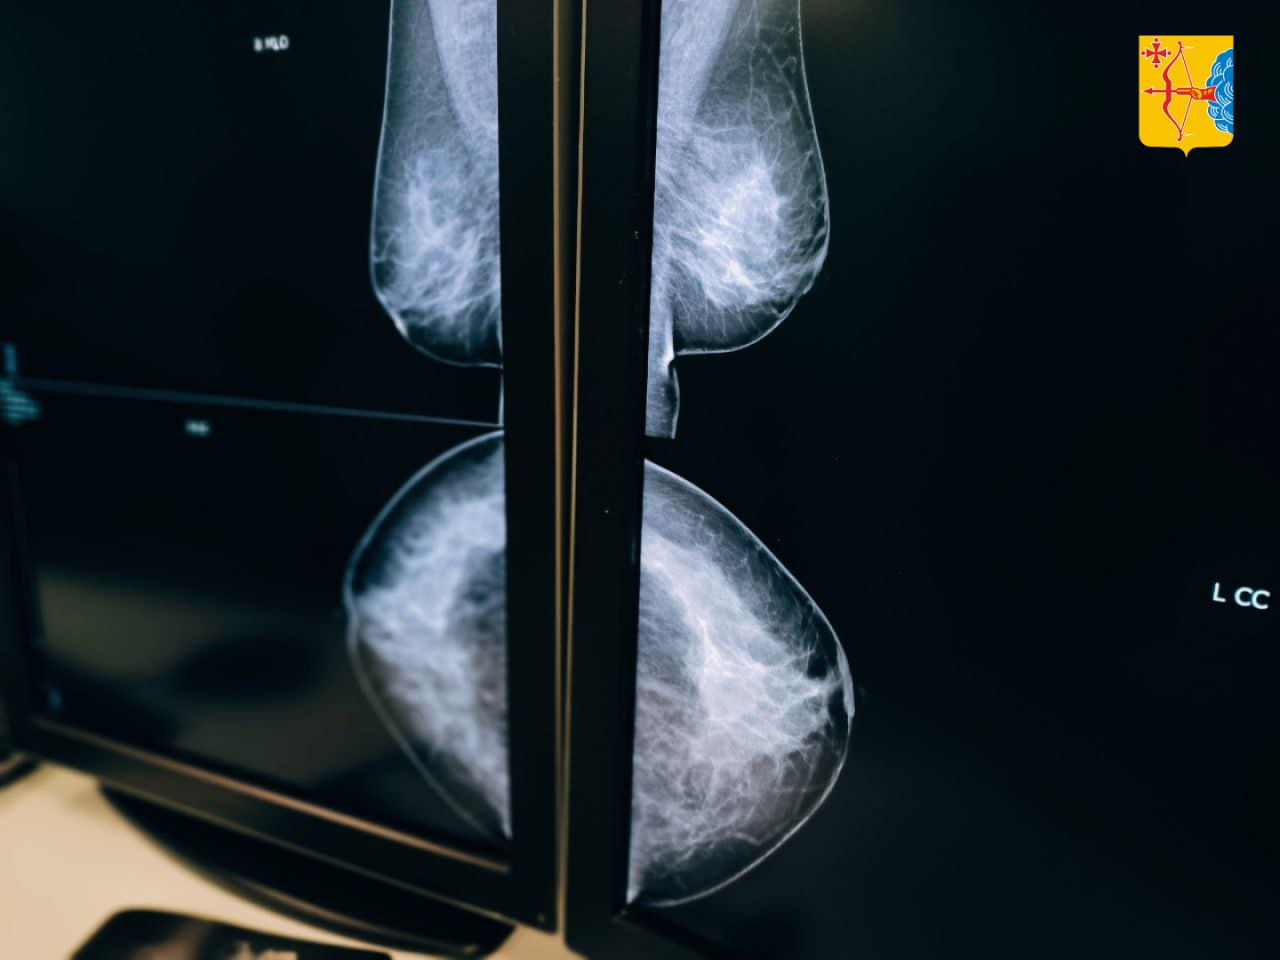

В этот день женщины могли бесплатно проконсультироваться со специалистами и пройти обследование. Всего осмотр прошли 182 человека, у пятерых заподозрили злокачественные образования. Для точной диагностики 100 женщинам сделали УЗИ, а 86 — маммографию.